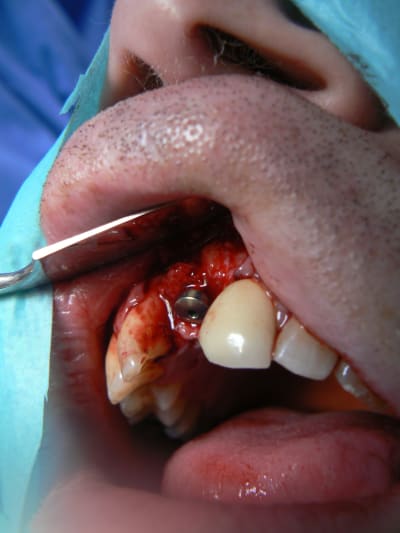

J'ai simplement peur que les vis de transfixation du greffon ne puissent provoquer son décollent au moment de leur dépose. En effet si de l'os vient se recréer entre les trois tétons, lors du dévissage ça peut provoquer un mouvement du greffon.

Bravo

j'ai retrouvé, mais c'est le correspondant qui à posé l'implant et les photos sont pas top :(

ceux sont les photos du correspondant .